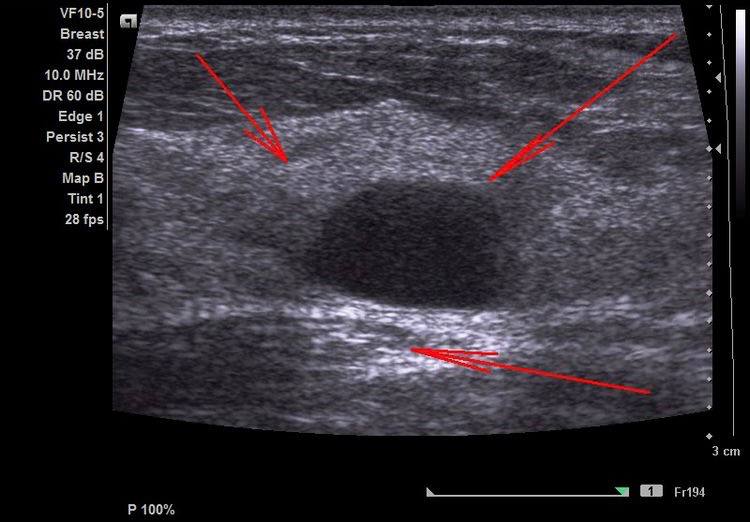

“32-річна львів’янка Роксолана два роки тому бавилася з донечкою і та випадково вдарила маму в область грудей. Жінка відчула нестерпний біль, який не минав кілька днів, тож вирішила звернутися до спеціалістів Лікарні Святого Пантелеймона. Під час УЗД медики виявили в лівій молочній залозі Роксолани фіброаденому. Це доброякісна пухлина, яка переважно виникає у молодих жінок до 35 років і здебільшого росте повільно”, – йдеться у повідомленні.

Зазначимо, що пацієнтки з фіброаденомою мають бути під постійним лікарським наглядом, аби вчасно виявити патологічні зміни і попередити ускладнення. Тому понад 2 роки Роксолана регулярно приходила профілактичні огляди і ті спостерігали за ростом пухлини. Коли утвір почав активно рости і досяг трьох сантиметрів, спеціалісти ухвалили рішення оперувати.